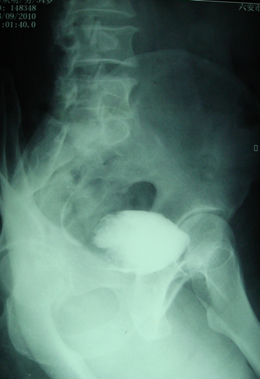

标题: CT28320:典型病例,男,56岁。无痛性血尿3月。 [打印本页]

典型病例,男,56岁。无痛性血尿3月。

膀胱占位性病变,呈菜花状生长,考虑膀胱癌。 期待病理。